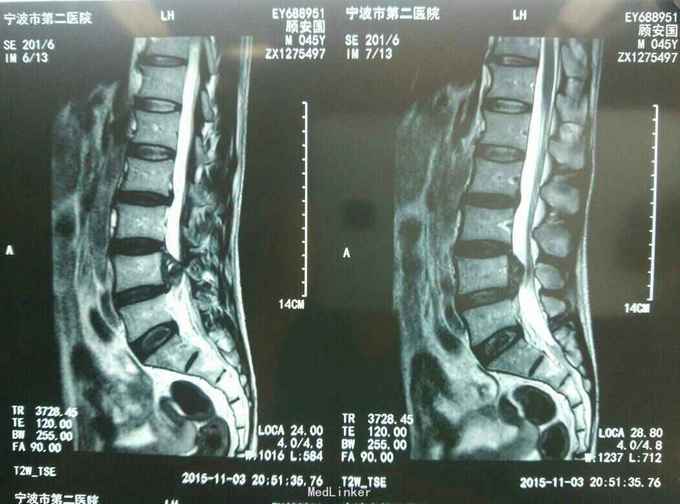

查体:L45间隙压痛,左侧小腿外侧及左足拇趾感觉减退,左下肢肌力四级,左侧下肢直腿抬高试验30度阳性。腰椎MR提示: L4/5椎间盘脱出向上高度游离,压迫左侧神经根。

诊断:L45腰椎间盘脱出游离。 治疗:行侧路椎间孔镜手术。